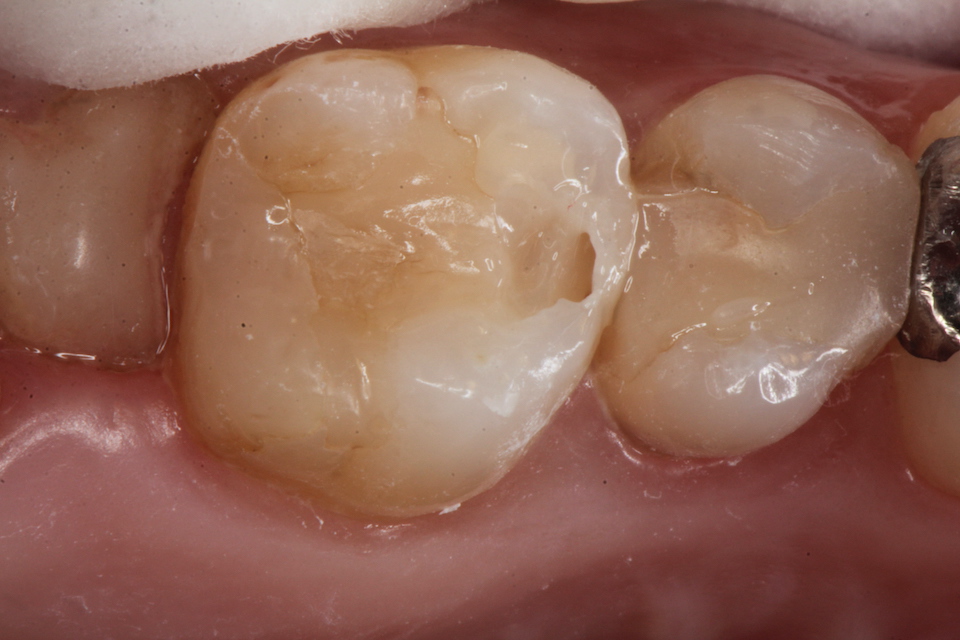

虫歯は金属の錆や腐食と同じ1.42 2025.11.10

虫歯は金属の錆や腐食と同じ1.41 2025.06.05